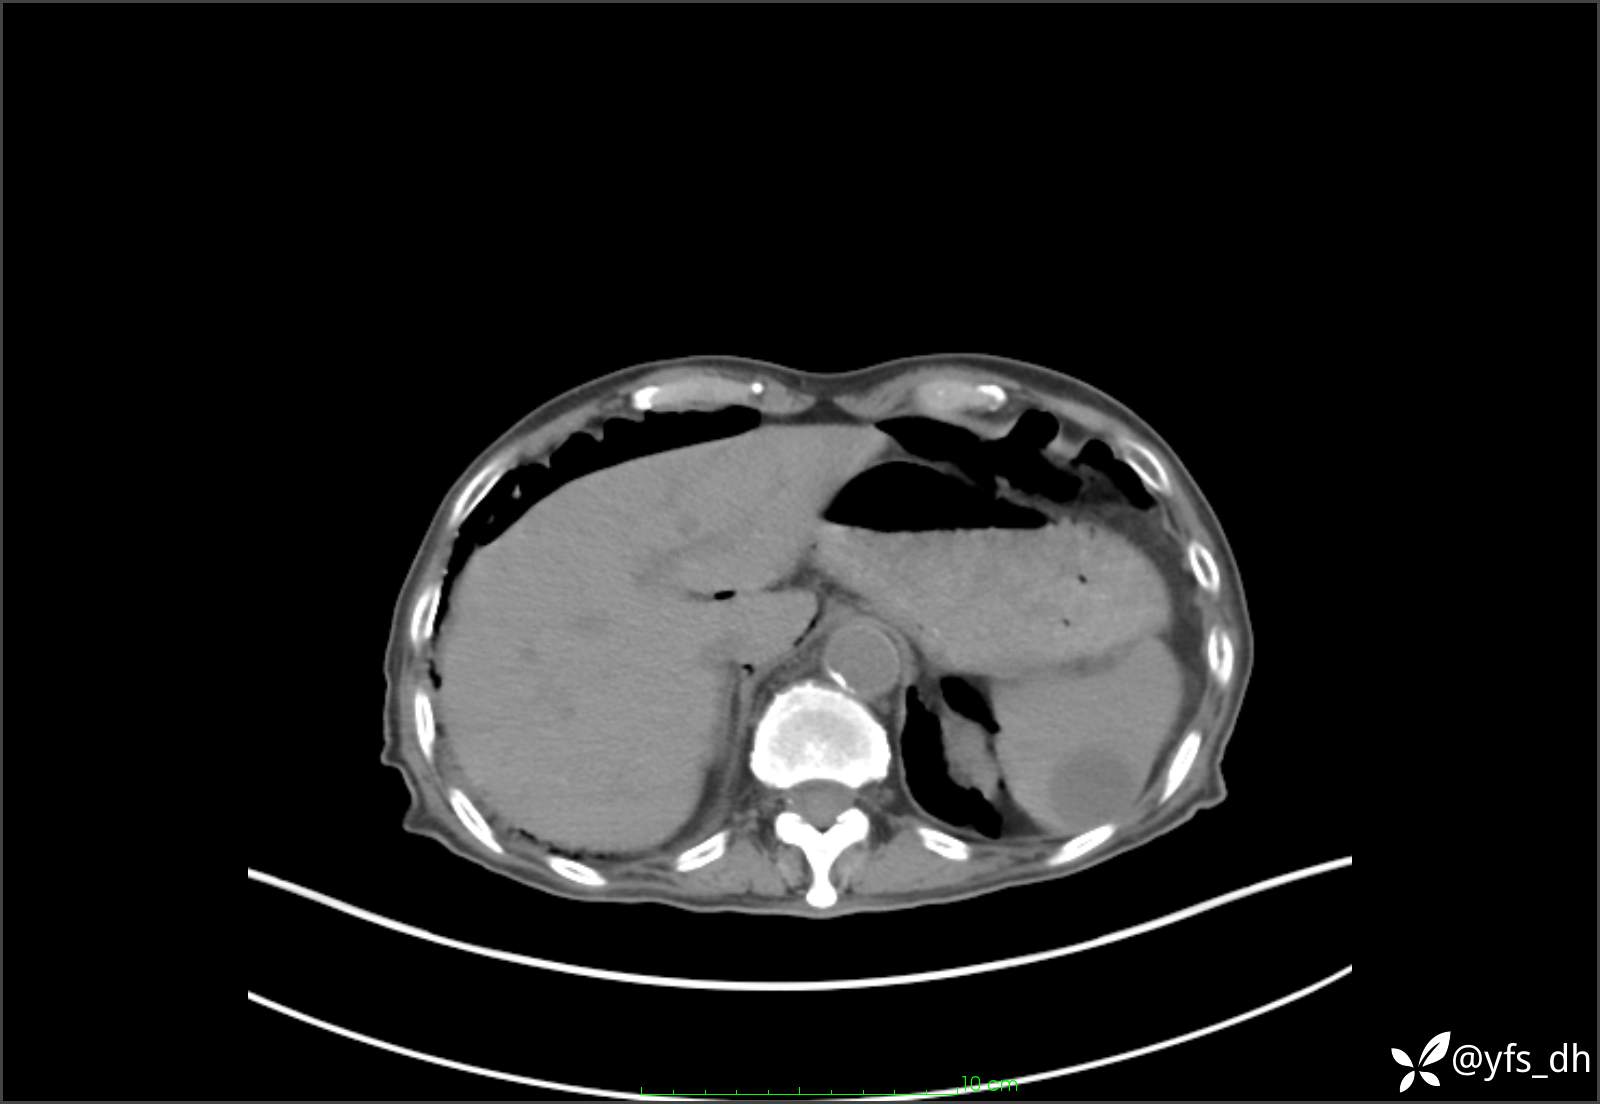

1.简要病史:患者4天前突发上腹部疼痛不适,但可以忍受。3小时前饭后突然加重,不能忍受后就诊。

2.简要手术记录:术中见腹盆腔大量肠液及粪便,乙状结肠中下段见一约3cm的破口。